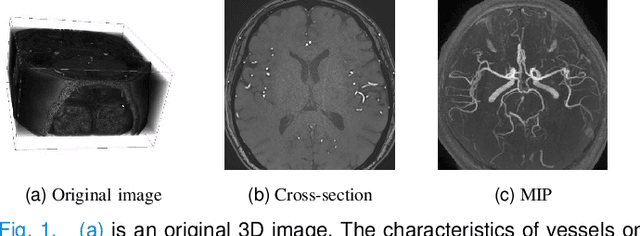

Abstract:Vascular structure segmentation plays a crucial role in medical analysis and clinical applications. The practical adoption of fully supervised segmentation models is impeded by the intricacy and time-consuming nature of annotating vessels in the 3D space. This has spurred the exploration of weakly-supervised approaches that reduce reliance on expensive segmentation annotations. Despite this, existing weakly supervised methods employed in organ segmentation, which encompass points, bounding boxes, or graffiti, have exhibited suboptimal performance when handling sparse vascular structure. To alleviate this issue, we employ maximum intensity projection (MIP) to decrease the dimensionality of 3D volume to 2D image for efficient annotation, and the 2D labels are utilized to provide guidance and oversight for training 3D vessel segmentation model. Initially, we generate pseudo-labels for 3D blood vessels using the annotations of 2D projections. Subsequently, taking into account the acquisition method of the 2D labels, we introduce a weakly-supervised network that fuses 2D-3D deep features via MIP to further improve segmentation performance. Furthermore, we integrate confidence learning and uncertainty estimation to refine the generated pseudo-labels, followed by fine-tuning the segmentation network. Our method is validated on five datasets (including cerebral vessel, aorta and coronary artery), demonstrating highly competitive performance in segmenting vessels and the potential to significantly reduce the time and effort required for vessel annotation. Our code is available at: https://github.com/gzq17/Weakly-Supervised-by-MIP.